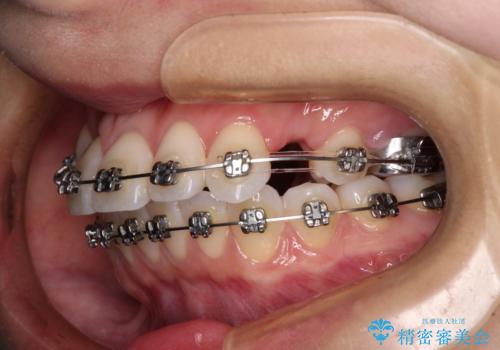

- メタルブラケット

- 2年10ヶ月

- 30回以上

奥歯の咬み合わせを維持しながら正中位置を改善するために、補助装置を使用しました。

予定より期間がかかりましたが、上下の正中位置を綺麗に一致させることができました。